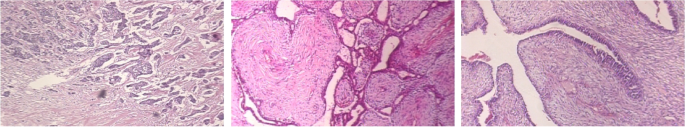

The Breast Cancer Histopathology Image Classification (BreakHis)68 dataset with 40\(\times \) and 100\(\times \) magnifications contain 8-classes: adenosis, fibroadenoma, phyllodes tumor, and tubular adenoma; ductal carcinoma, lobular carcinoma, mucinous carcinoma, and papillary carcinoma. The samples of this dataset are exemplified in Fig. 6.

An experimental study has been carried out on two more public datasets for human medical image analysis. The BreakHis with 40\(\times \) and 100\(\times \) magnifications68 and SIPaKMeD69 datasets have been evaluated for generalization. The SIPaKMeD dataset69 is useful for classifying cervical cells in pap smear images, illustrated in Fig. 7. This dataset is categorized into five classes based on cytomorphological features using the proposed PND-Net. The conventional classification results are given in Table 4, and the performances of cross validations are provided in Tables 6 and 7.